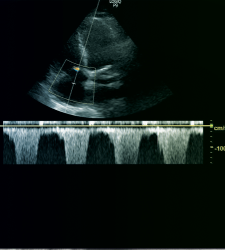

Certificat d’Echographie Appliquée au Patient Critique

Le Certificat d’Échographie Appliquée au Patient Critique est une formation unique en Belgique francophone, reconnue internationalement, destinée aux professionnels de la santé souhaitant maîtriser l’échographie clinique dans des contextes critiques.

Niveau 1 : Formation de base sur l’utilisation de l’échographie clinique chez le patient critique, incluant l’évaluation cardiaque, pulmonaire, abdominale, vésicale, des grands vaisseaux, ainsi que la pose de cathéters écho-guidée. Ce niveau comprend trois journées de cours, réparties sur deux vendredis et un samedi, avec des exercices pratiques encadrés totalisant jusqu’à 56 heures.

Niveau 2 : Formation avancée accessible aux participants ayant réussi le niveau 1 ou possédant une maîtrise attestée de l’échographie. Ce niveau couvre l’évaluation hémodynamique, l’échographie transcrânienne, l’échographie en arrêt cardiaque et les bases de l’anesthésie loco-régionale écho-guidée. La formation s’étend sur quatre journées, réparties sur deux vendredis et samedis.

- Le niveau 1 est une formation universitaire de base. Cette formation permet l’apprentissage de base de l’échographie clinique. Cette formation permet la familiarisation avec l’outil échographique, enseigne les principales coupes échographiques utiles dans la médecine critique ainsi que la reconnaissance des patterns pathologiques pathognomoniques.

- Le niveau 2 est une formation universitaire élargie permettant l’acquisition de compétences avancées en échographie critique. Cette formation permet d’acquérir les bases pour une évaluation hémodynamique du malade critique ainsi que certaines compétences spécifiques de la médecine critique telles que l’échographie transcrânienne, l’échographie en arrêt cardiaque où encore les bases de l’anesthésie loco-régionale écho-guidée. Cette formation permet aussi la supervision de la formation de niveau 1 et le développement de l’échographie appliquée à la médecine critique dans les services d’anesthésie, soins intensifs où d’urgence

Le niveau 1 offre une formation de base introduisant l’utilisation de l’échographie clinique chez le patient critique, couvrant l’évaluation cardiaque, pulmonaire, abdominale, vésicale, des grands vaisseaux ainsi que la pose de catéteres écho-guidée.

> Fenêtres cardiaques

> Ventricule Gauche

> Ventricule Droit

> Veine cave inférieure

> Mesures fonction gauche

> Les mesures hémodynamiques : le débit cardiaque – la fonction cardiaque (EF / Simpson) – les pressions de remplissage